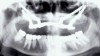

The Toronto Conference in 1982, chaired by Professor George Zarb and presented by Professor Per-Ingvar Brånemark, was a seminal event that changed edentulous treatment planning concepts irrevocably. No longer was it necessary to rebuild lost bone through grafting alone in either arch. The severely atrophic mandible, for example, could be treated with as few as four implants used to support a bone-sparing prosthesis through integrated tooth analogs, as demonstrated in Figure 1 through Figure 3. Here, an 81-year-old patient presented with severe mandibular atrophy (Figure 1) from denture wear since a very young age and had a history of being unable to manage a mandibular prosthesis despite numerous attempts at new denture construction. Four vertical machined-surface osseointegrated implants were placed in 1983 by Professor Brånemark, and all four penetrated the inferior cortex up to 3 mm to 4 mm in depth, as shown on the immediate postoperative panoramic film (Figure 2). At 4 years and 5 months, reparative bone had formed to the apices of all implants (Figure 3), and all of them remained in uncompromised function until the patient passed away at age 90.

Fig 2. Four vertical machined-surface osseointegrated implants placed in 1983 penetrated the inferior cortex up to 3 mm to 4 mm in depth, immediate postoperative.

Figure 2

Fig 3. At 4 years and 5 months follow-up, reparative bone had formed to the apices of all implants.

Figure 3